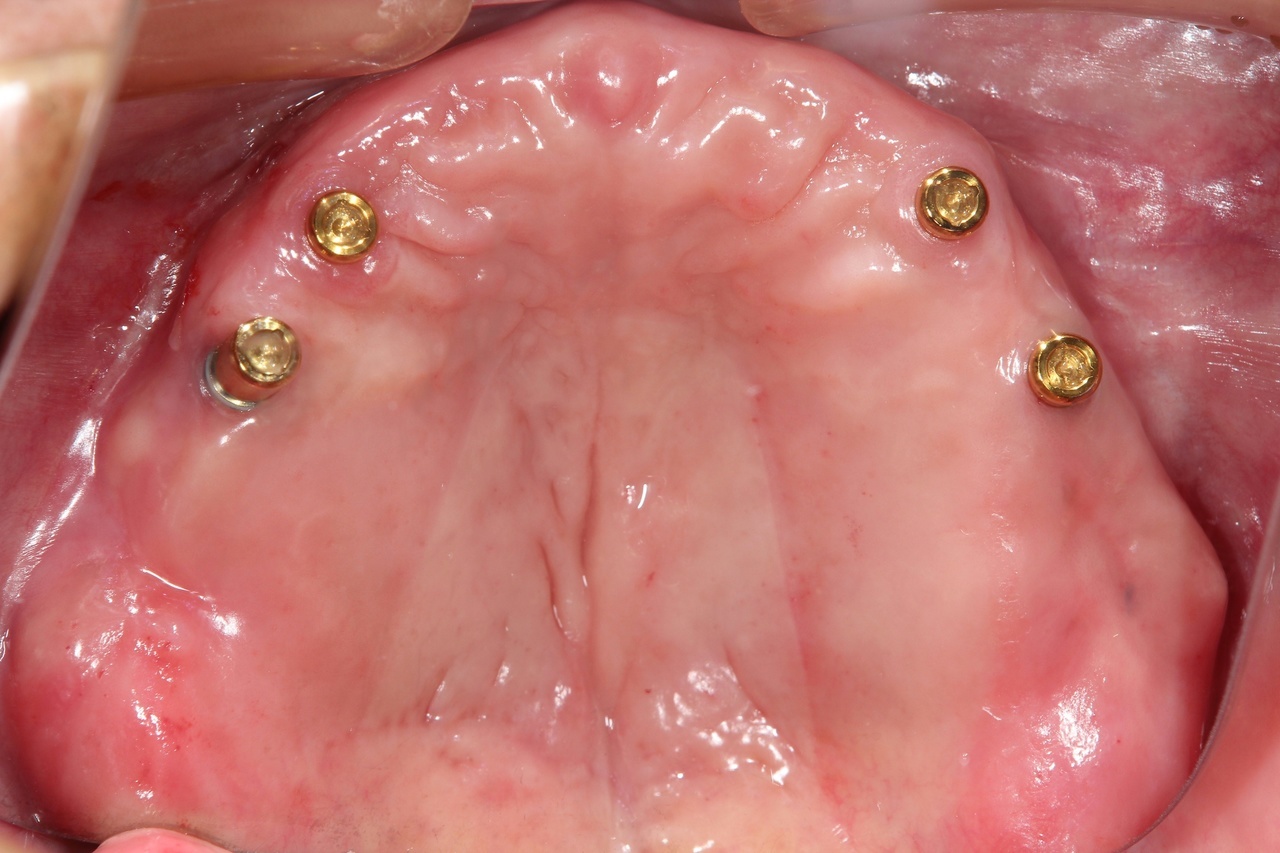

インプラントオーバーデンチャー<ロケータータイプ> (沼津市在住 男性)

インプラントを埋め込み、固定用のロケーターを装着し、入れ歯をしっかりと固定する治療法です。

少ない本数でがっちり噛める治療法です。取り外し可能でしっかり固定できるので、入れ歯の誤飲の心配がなく、手入れがしやすいので寝たきりになっても安心に使用出来ます。

しっかり噛むことで踏ん張りがきくので転んで骨折するリスク回避にもなります。

● オーバーデンチャーを外した状態

● オーバーデンチャーを付けた状態

インプラントオーバーデンチャー